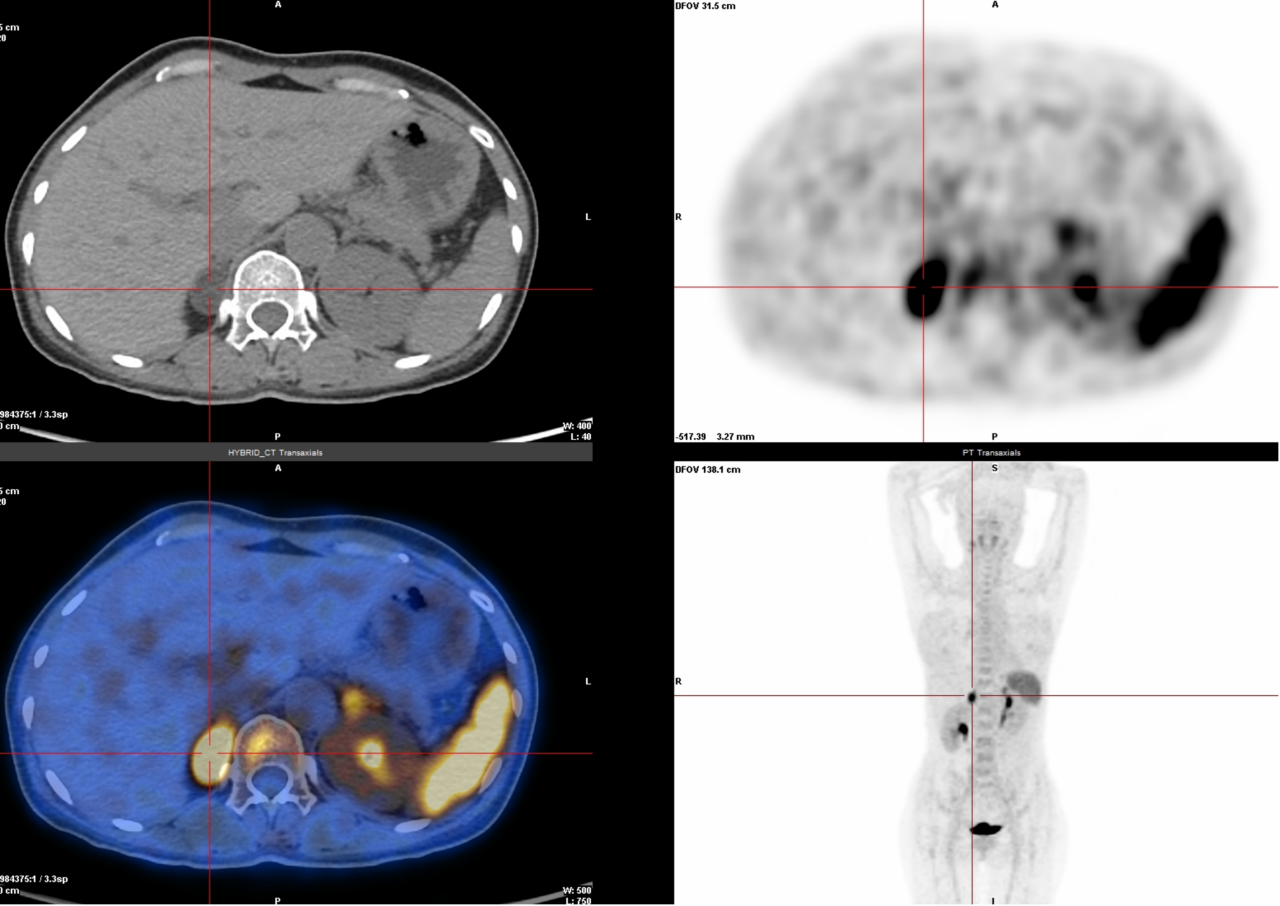

2.多种癌症检查(68Ga-FAPI):能检测很多种癌症,尤其是肝癌、胃肠印戒细胞癌、腹膜转移癌等,因为它能精准找到肿瘤周围的特殊细胞(成纤维细胞)。

△腹膜转移癌